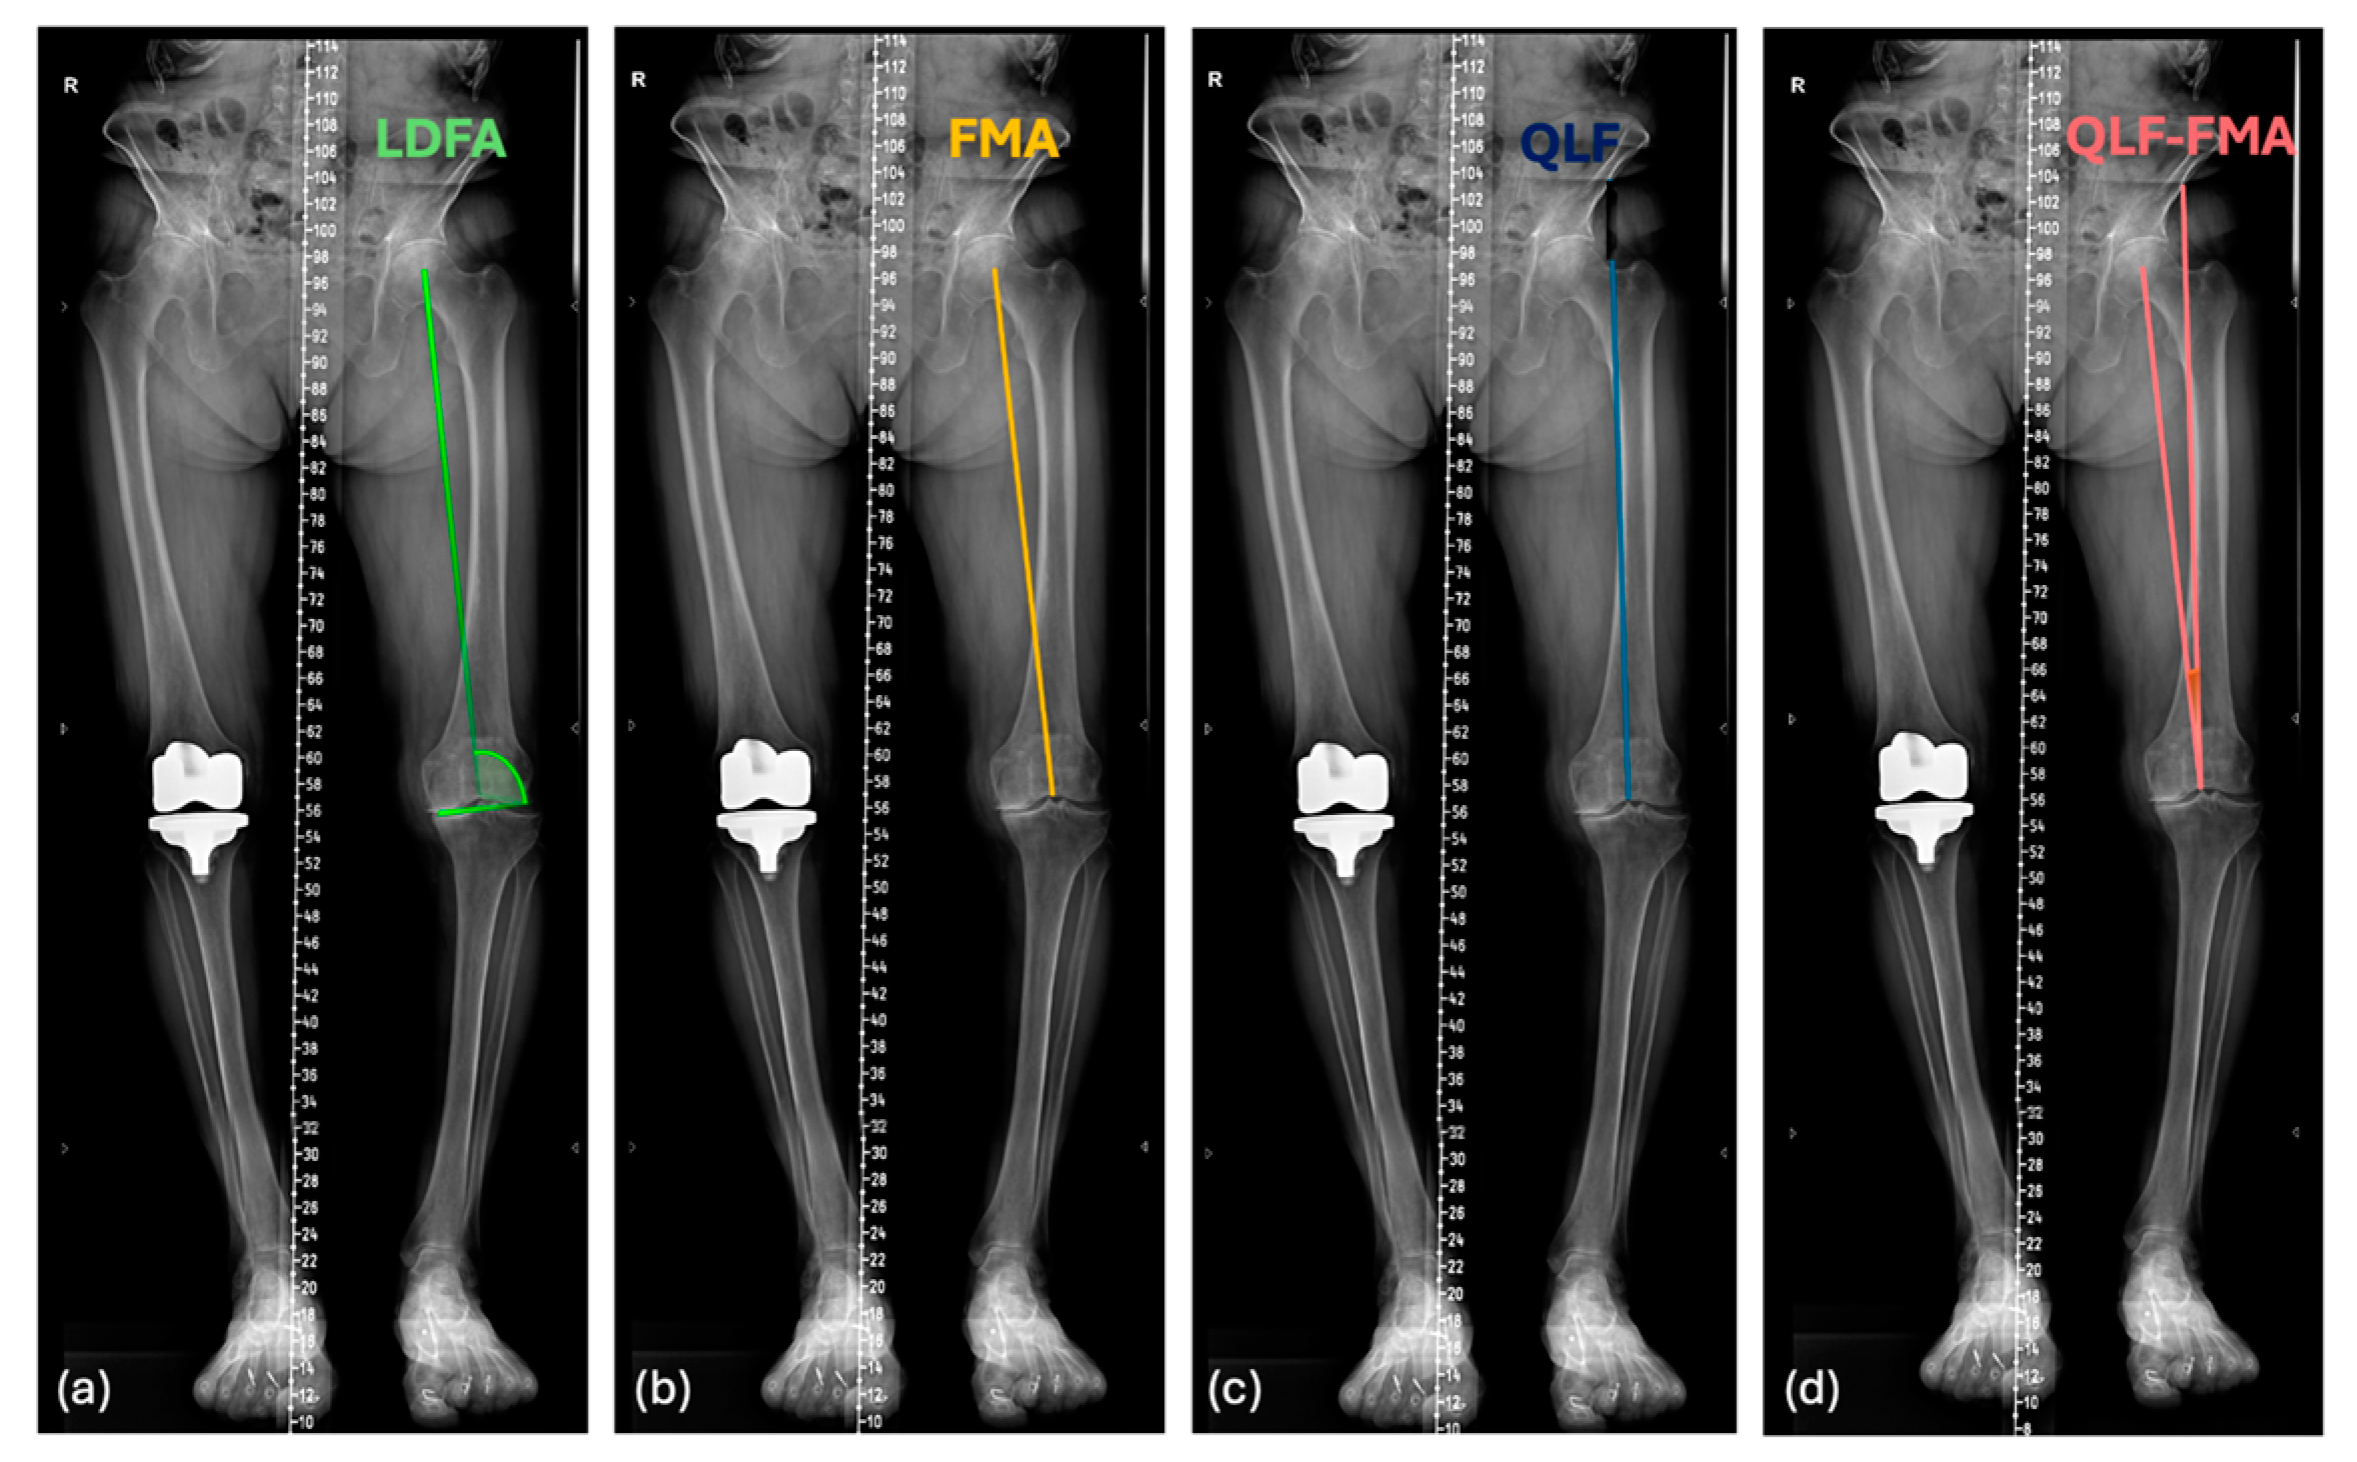

2.2. Preoperative Radiographic Measurement

2.3. Mathematical Formula for the Prediction of Postoperative PTA Orientation